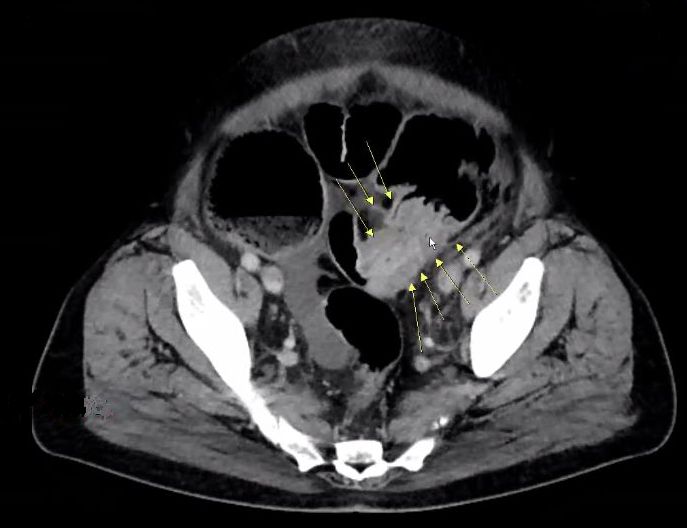

| Metastasen | zahlreiche vergrößerte Lymphknoten paraaortal, paracaval und mesenterial.![]() |